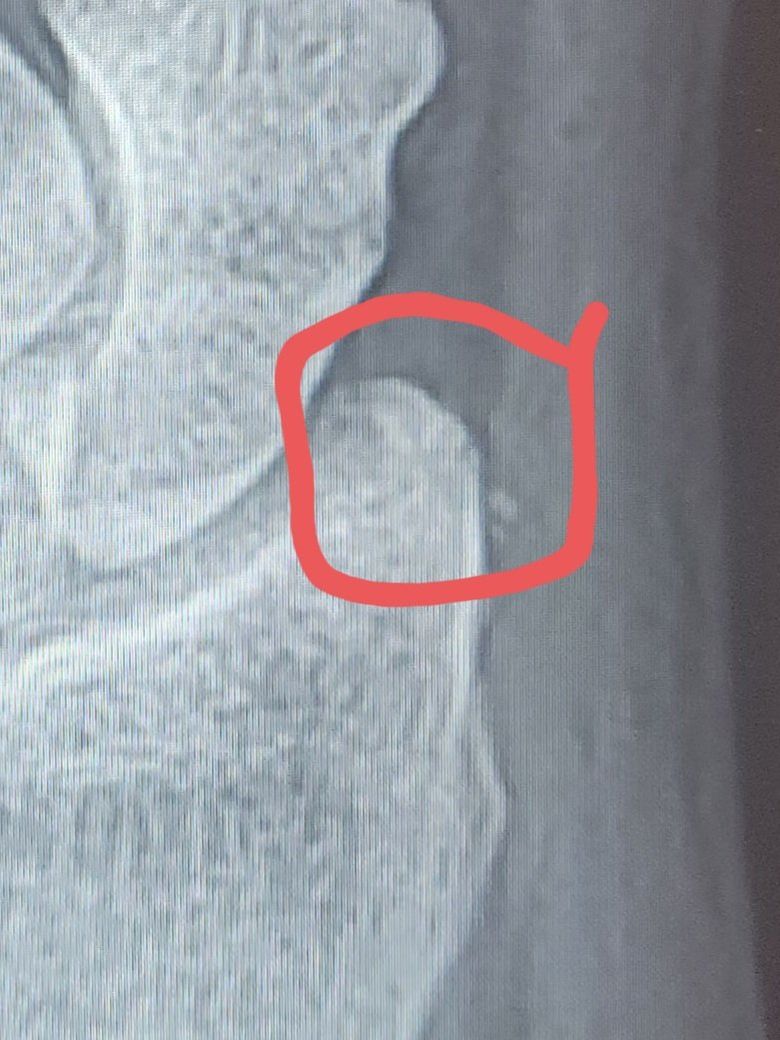

엑스레이 다시한번만더 봐주세요

판독부탁드립니다..씨티찍을돈이없어요ㅜ

골절 의심부위는 빨간색체크부분인데

판독부탁드립니다

골절 의심부위는 빨간

색체크부분인데 뭔가있는거같아요

ㅠㅠ..빠른답벼ㆍ해주시면 감사합니다